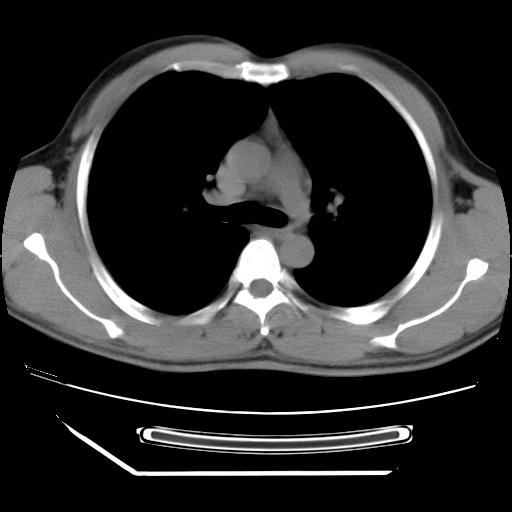

男,38岁,于2009年8月9日晚突发左侧胸痛,今x线提示左下肺阴影,为了明显确诊断,行ct检查,

血常规:嗜酸性细胞增高,单核细胞增高。

病灶发生在下叶,密度均匀,边缘模糊、毛糙,周围血管纹理增强扭曲改变,靠近胸膜处病灶胸膜反应明显。

支持考虑---球形肺炎。

左肺舌叶病变。主体病灶呈类圆形中心密度低,成液化趋势周边班片影分布

考虑肺脓肿

虽然实验室检查支持炎性病变,且病变内有坏死改变(中央呈大片状低密度影),但仍不能掉以轻心,鳞癌也可以有这种影像改变。